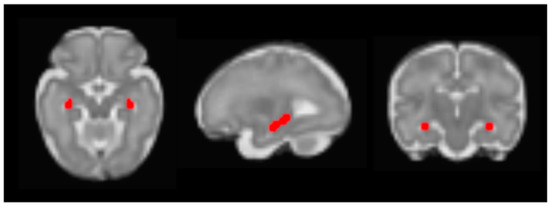

| X | Y | Z | Intensity (Fisher Z) | Direction of Effect | |

|---|---|---|---|---|---|

| Prenatal Distress | |||||

| Right posterior parietal association cortex | 30 | −28 | 6 | 3.83 | Positive |

| Prenatal Cortisol AUCg | |||||

| dACC | 2 | 16 | −2 | 2.83 | Positive |

| Left mPFC | −12 | 24 | −6 | 2.64 | Positive |